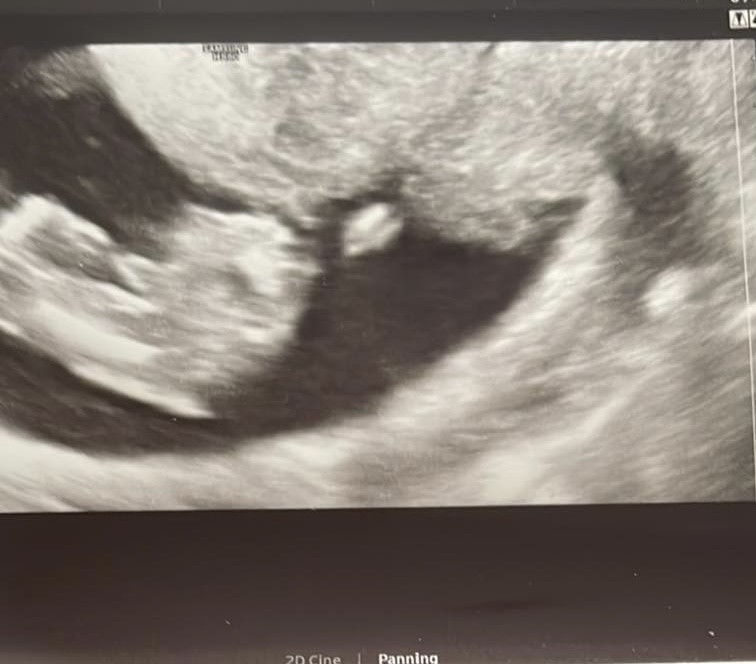

Chłopiec czy dziewczynka?

Hej jestem w 14 tygodniu ciąży. Miałam dziś robione usg doktor stwierdził ale nie potwierdził w 100% że na usg widać że to chłopczyk. Podsyłam zdjęcie pomóżcie może ktoś będzie umiał określić lepiej

• E46EA7BD-D03B-4E85-9701-4EA7FE72D5FC.jpeg